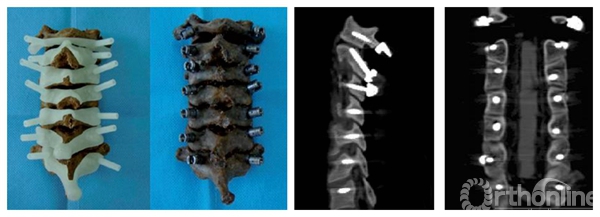

通过Geomagic studio12参考最佳进钉点所在的位置,提取椎体后部解剖形态,设计与椎板后部解剖形态一致的反向模板(图2),与椎弓根植钉通道拟合为一体,形成带有定位定向管道的数字化导航模板。在三维重建椎体模型上即可以进行虚拟植钉手术操作。再通过光固化成型技术(SLA)生成实模板体即可以辅助术中应用。在临床应用时可以确保每一枚螺钉正确的置入位置和方向(图3),真正体现了颈椎椎弓根螺钉置入的个体化原则。我们的临床应用范围已经包括了从上颈椎、胸腰椎到脊柱侧弯矫形等多个方面。

图3 虚拟模板通过SLA技术生成实体,辅助尸体实验及术后X线影像

辅图 尸体标本经模板辅助椎弓根植钉后的CT影像显示椎弓根钉位置良好

临床研究发现,每个导航模板都和相应椎体后部骨性解剖结构十分贴合,所有椎弓根螺钉置入较为满意。术后CT扫描发现椎弓根螺钉完全位于椎弓根内,进钉点准确、进钉角度恰当,螺钉长度及直径合适,无穿破椎弓根皮质及椎体前方的螺钉,患者无周围组织损伤症状。个体化的脊柱椎弓根导航模板对于手术医师只要将模板和暴露的椎板相贴合, 就可以进行钉道准备, 并不依赖于个人经验。模板的制作是个体化的制作, 可采用定制的方式, 因此临床上有应用方便,为颈椎椎弓根的定位提供了一种全新的方法。(如图4、图5)。

图4 术后X线及CT影像